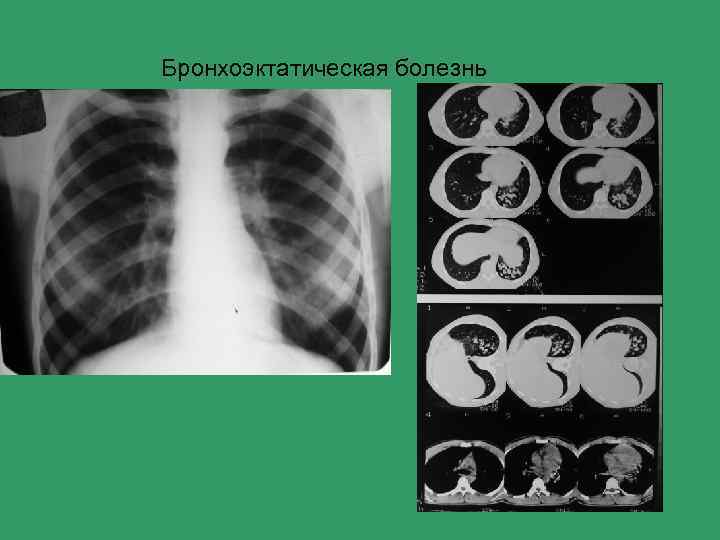

Бронхоэктатическая болезнь